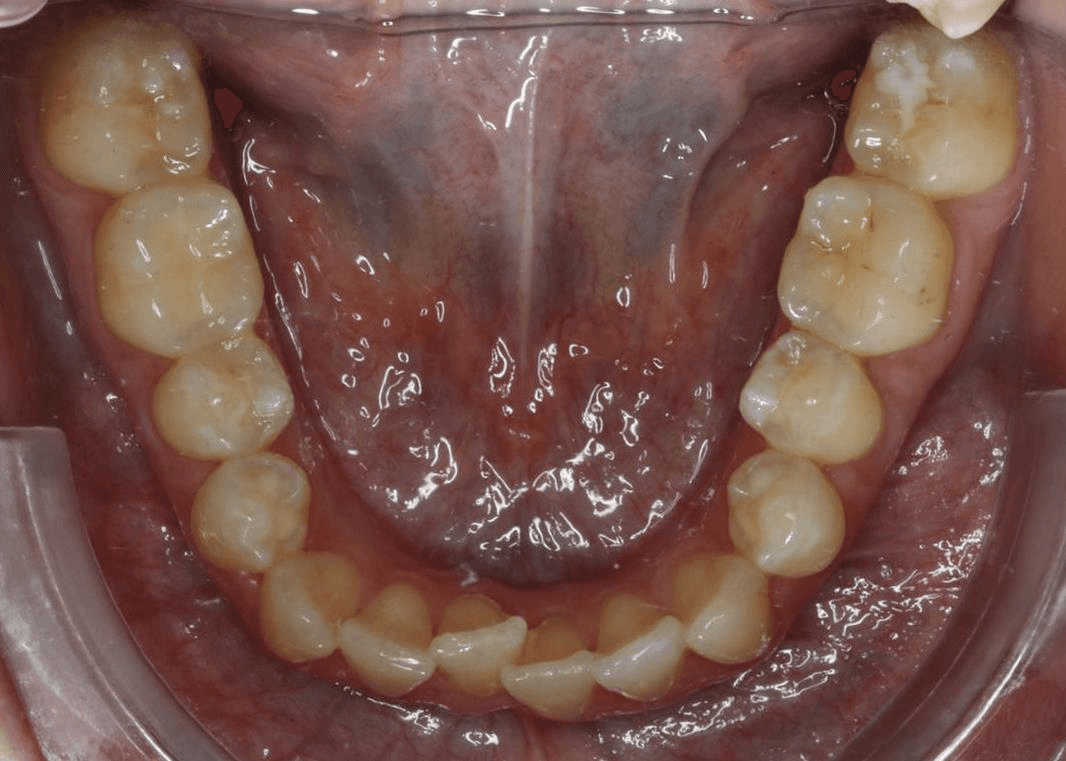

Initial treatment

INTRAORAL

Diganosis: Moderate crowding in both arches, constricted arch forms with anterior and posterior single tooth crossbites, poor smile display